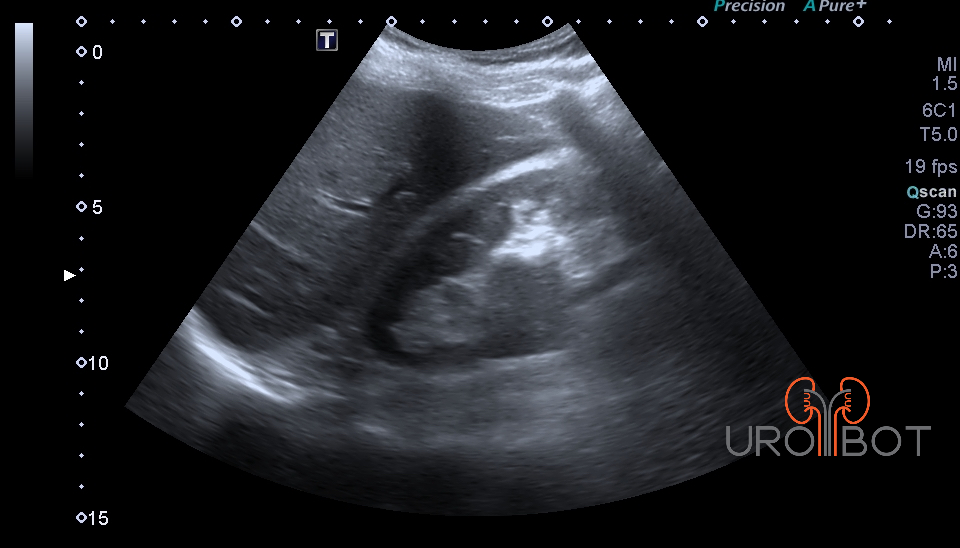

In der Früherkennung ist der Ultraschall die führende Untersuchung. Ab einer Größe von 2 cm kann man bereits bösartige Tumore von gutartigen Zysten unterscheiden. Doch obwohl die Qualität der heutigen Ultraschallgeräte stark zugenommen hat, wird man zu weiteren Unterscheidung und Klassifizierung radiologische Verfahren wie die CT (Computertomographie) oder aber die MRT (Magnetresonanztomographie) einsetzen.

Das Video zeigt eine sonographische Untersuchung der rechen Seite mit Nachweis eines großen Tumorthrombus in der unteren Hohlvene.